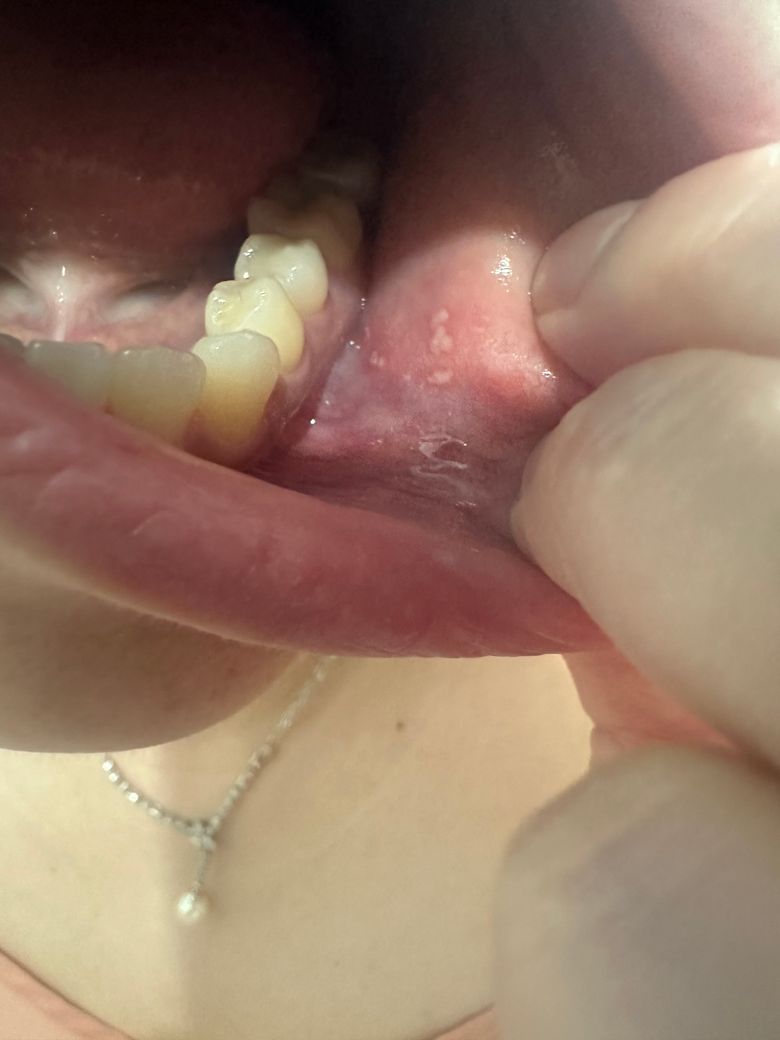

제발 알려주세요 항상 생리 전 입안에 이런게 생깁니다 ㅠ ㅠ

한 이년전부터 생리 전 10흘쯤? 부터 생리 기간 중

꼭 입안에 사진처럼 하얀 점 막이 여려곳에 생겨요

평소 알던 구내염이란건 아파야 하잖아요

근데 이건 전혀 통증도 없고

하얀막이 자동 탈락 되고 그 자리가 약간 붉다 돌아와요 ㅠ ㅠ

억지로 살살 벗기면 벗겨져요 통증도 없고 ㅠㅠ

• 1번 째 사진